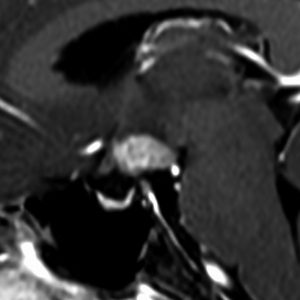

ICE化学療法投与開始から数日で小さくなります

この例は古いので第3脳室開窓術 ETV をしていません。左はICE化学療法前。中央は9日後。右は25日後です。閉塞性水頭症があっても1週間くらいで中脳水道が通って水頭症は改善します。ジャーミノーマであれば,ICE化学療法1コースでかなり縮小するはずです。このような顕著な効果がない時には,逆にジャーミノーマ以外の胚細胞腫瘍が混在していると考えた方がいいでしょう。多くは奇形腫の混在です。